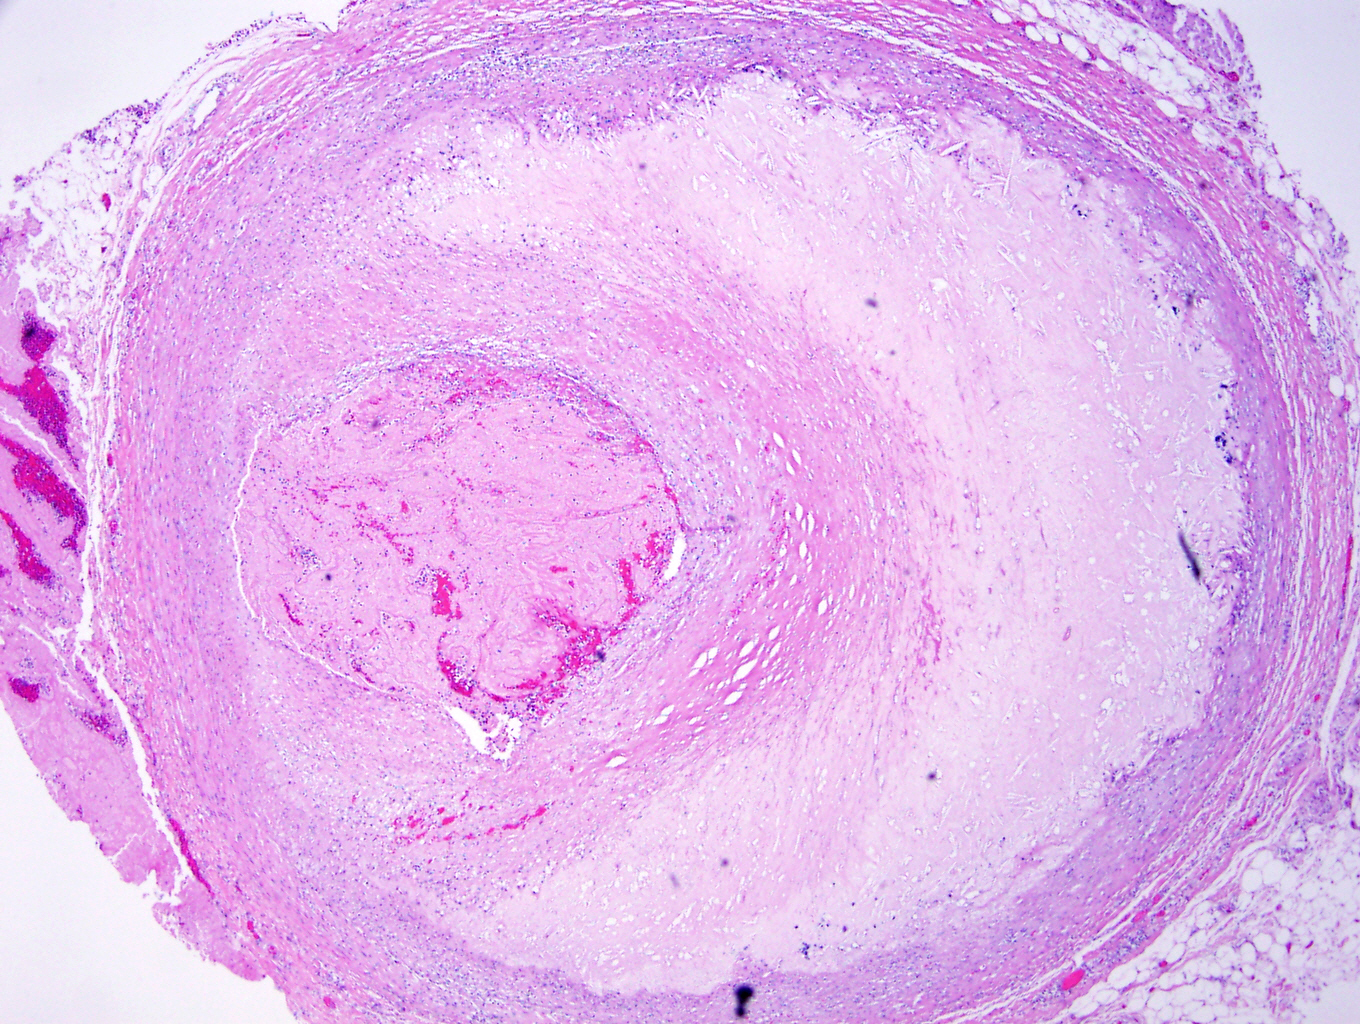

Microscopic (histologic) description

- Fatty streak: subendothelial accumulation of foam cells without necrotic core or fibrous cap

- Fibrous cap atheroma (Am J Med 2009;122:S3):

- Well formed necrotic core with overlying fibrous cap; smooth muscle cells, macrophages, lymphocytes and connective tissue components may be present

- With rupture: luminal thrombus communicates with underlying necrotic core

- With erosion: luminal thrombosis; no communication of thrombosis with necrotic core

- Fibrocalcific plaque: collagen rich plaque, contains large areas of calcification with few inflammatory cells, necrotic core may be present

Microscopic (histologic) images